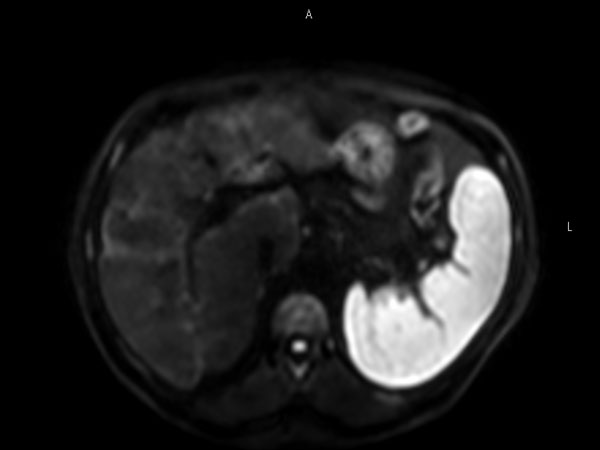

62 year old patient with huge, non-cirrhotic liver tumor. Question is if the portal vein is closed or not which has a direct influence on treatment options. Portal vein turned out to be open and patient was referred for embolization. No other tumors / lesions were found.

Axial  dynamic mDIXON (post-gado)